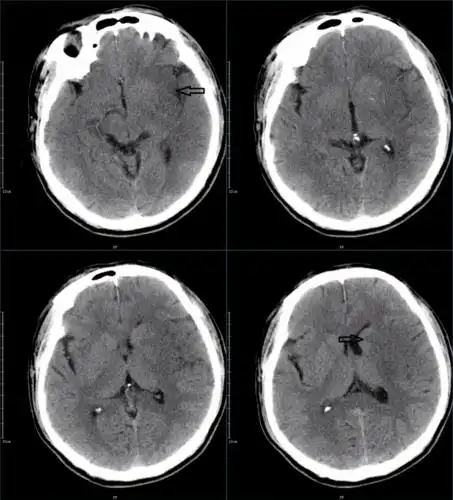

67超急性期大面积脑梗死ct平扫表现